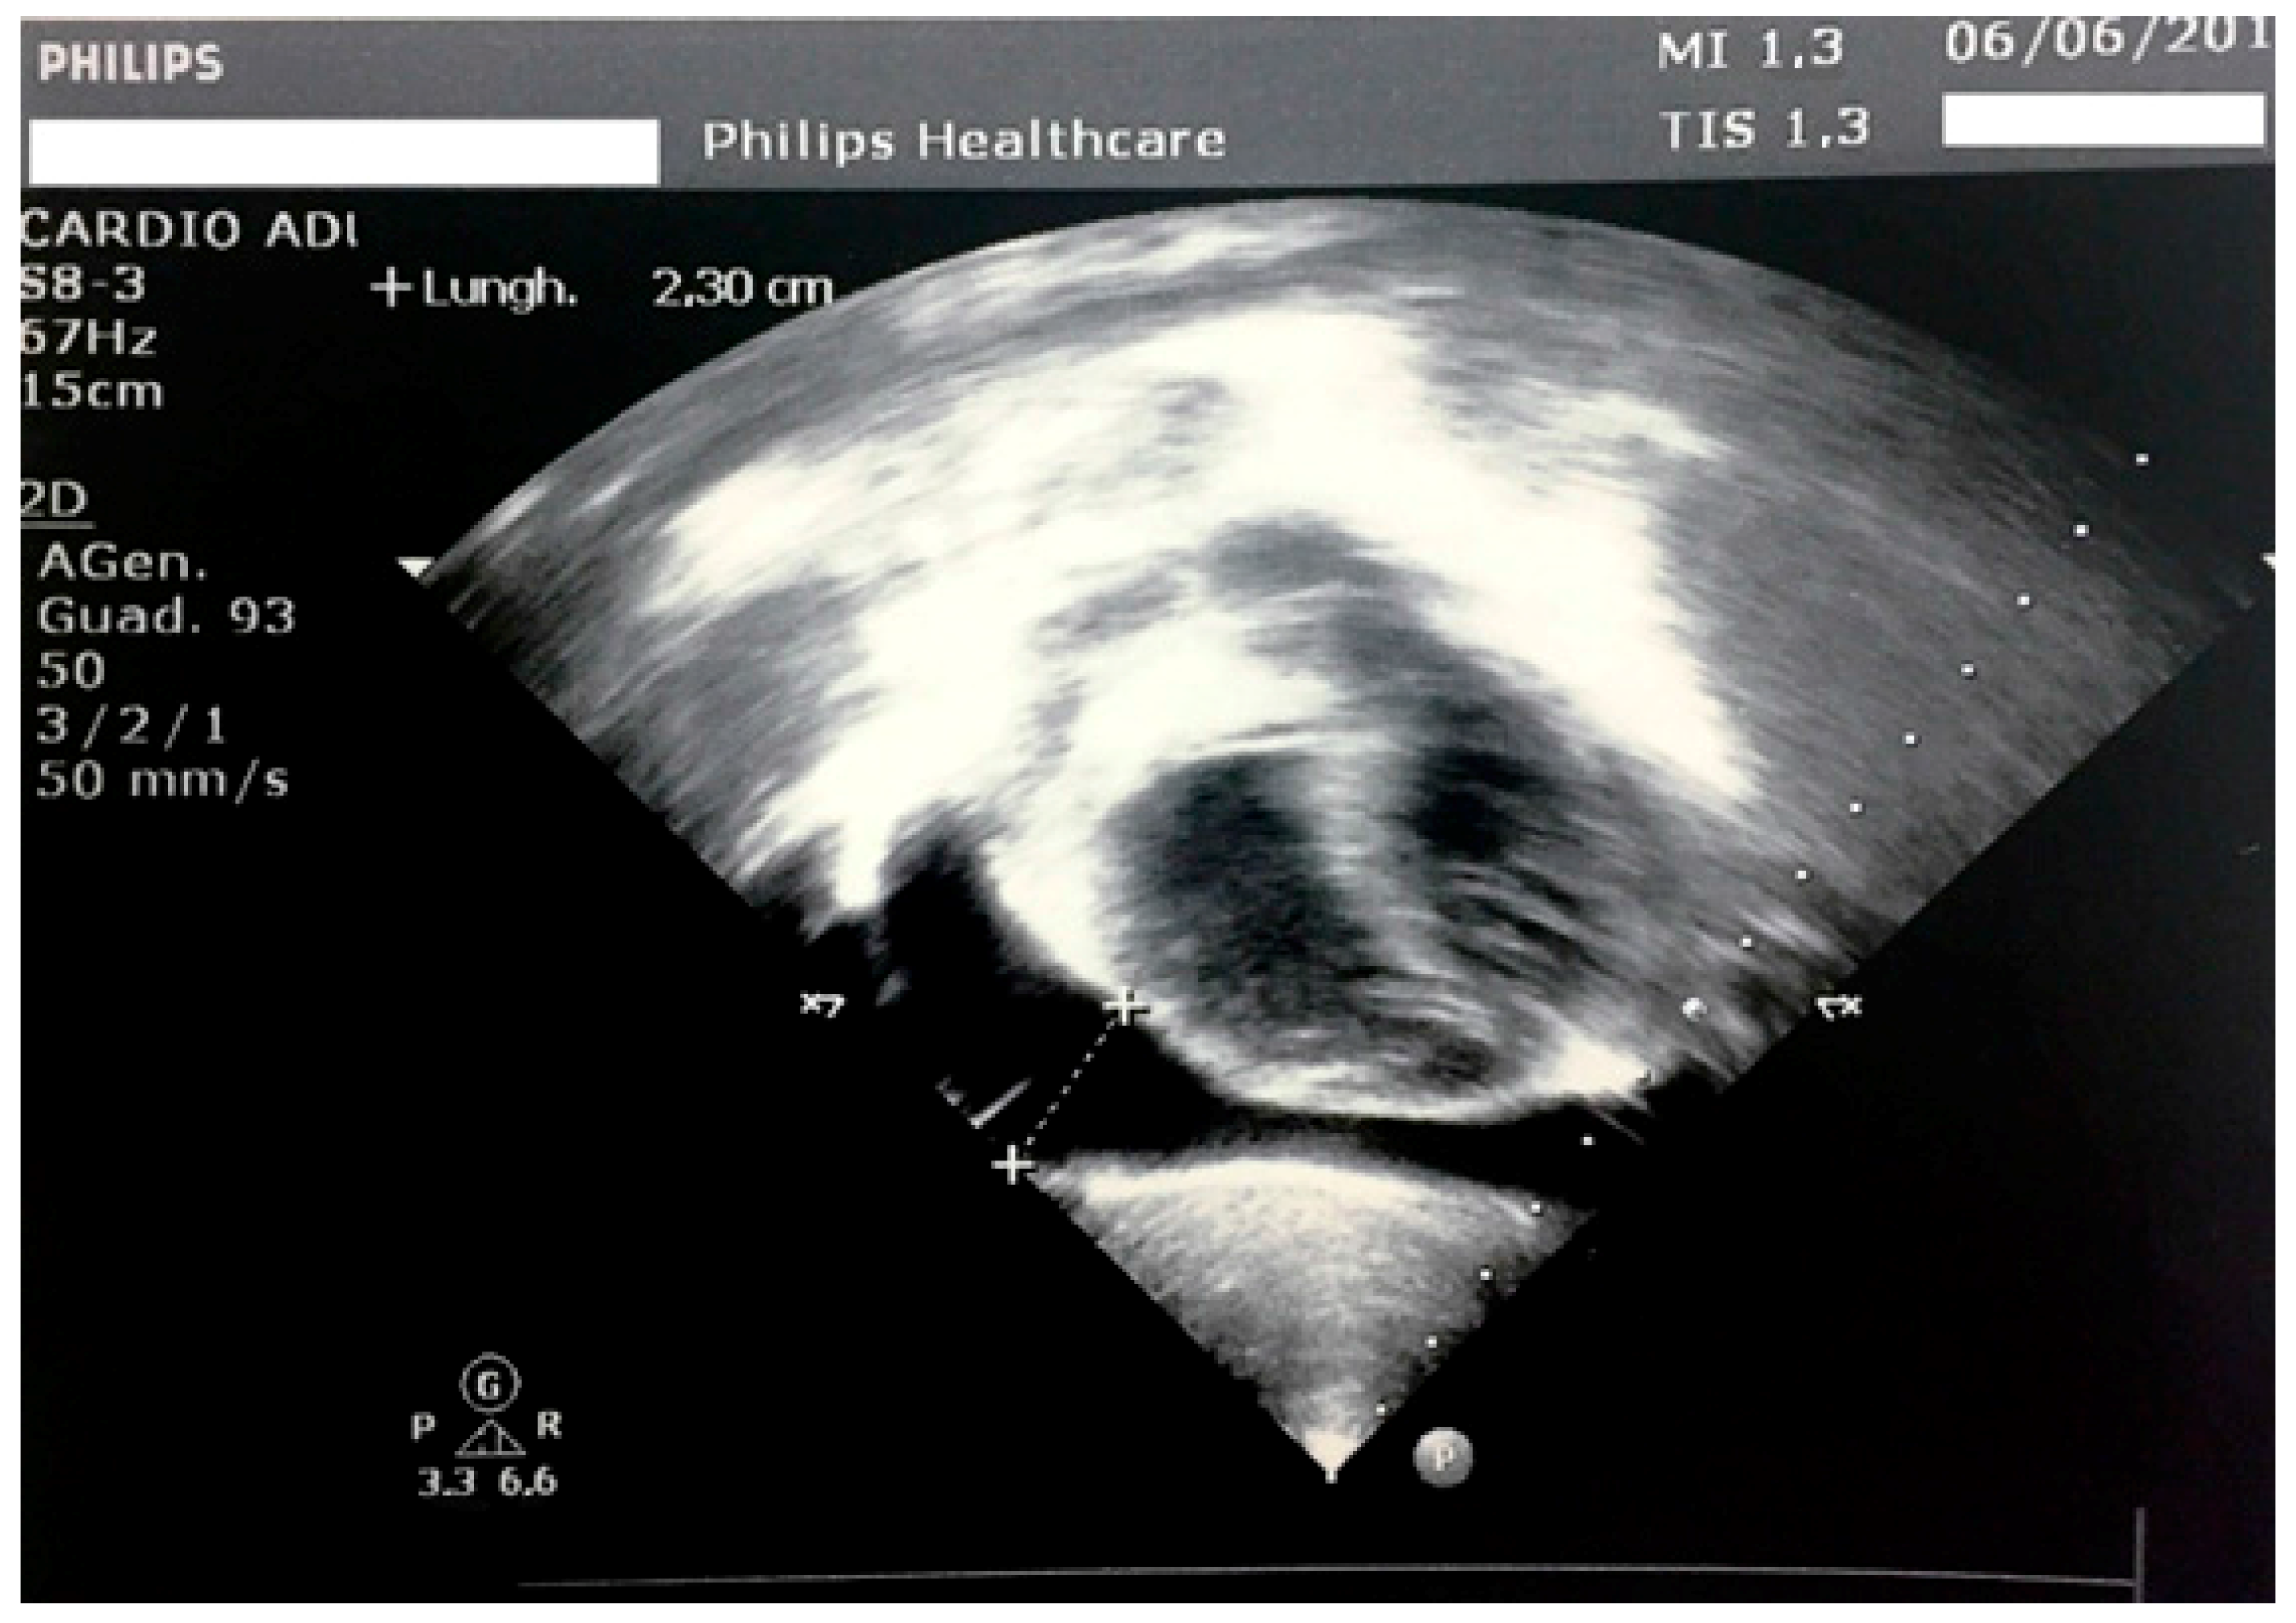

In the hospital, the clinical examination did not reveal any pathological signs other than a palpable thyroid. He had a normal heart rhythm with an innocent systolic heart murmur without pericardial rubs. The lungs were clear to auscultation and percussion bilaterally. The abdomen was soft, nontender, and nondistended. No pathologic signs were identified in the neurologic examination. Vital signs showed a pulse of 80 bpm (<2 standard deviation (SD) for age), a respiratory rate of 16 breaths/minute, SpO2 of 100% in room air, temperature of 36.5 °C, and blood pressure of 94/57 mmHg. His weight was 21 kg (78th percentile, 0.78 SD), his height was 101.8 cm (12th percentile, −1.18 SD), and his body mass index (BMI) was 20.26 (96th percentile, 1.76 SD) according to the Italian Society for Paediatric Endocrinology and Diabetes charts [11]. The mid-parental height was 166.0 cm (−1.63 SD). His bone age was delayed by one year with respect to the chronological age. On the chest radiograph, the heart had a globular appearance, and the lung fields were normal. An echocardiography confirmed and determined the effusion amount (max, 23 mm; 600 mL) with light impairment of the heart kinetics (Figure 1).

The ECG showed sinus bradycardia with a normal ST tract. However, QT dispersion corrected for heart rate was longer than in normal subjects (90 ms). According to the European Society of Cardiology guidelines, it was possible to exclude acute pericarditis due to the absence of at least two major criteria among pericarditic chest pain, pericardial rubs, widespread ST-elevation or PR depression on ECG, and pericardial effusion [12]. As the duration of effusion was unknown, whether it was incessant, recurrent or chronic could not be evaluated. Pericardialcentesis was not performed because the child was in good clinical condition and could be continuously monitored. Based on the blood test results, an infectious cause of the pericardial fluid excess was considered unlikely. The white blood cell count was 5920/mm3, the lymphocyte count was 60.5%, the neutrophil count was 33.8%, and C-reactive protein (CRP) and the erythrocyte sedimentation rate were in the normal range. In addition, pharyngeal swabs for respiratory pathogens, the Mantoux test, and IgM antibodies against cytomegalovirus, Epstein-Barr virus, adenovirus, parvovirus B19, and Mycoplasma pneumoniae were all negative. General biochemical examinations revealed minor creatine phosphokinase (510 U/L) and aspartate aminotransferase (55 U/L) elevation. Serum electrolytes were in the normal range (Na 138 mEq/L, K 4.9 mEq/L, Cl 96 mEq/L) Renal function indexes and anti-nuclear antibodies (ANA) were found to be normal. Thyroid function testing revealed very high thyrotropin (TSH, 487 μIU/mL; normal range, 0.340–5.600 μIU/mL) and low serum-free thyroxine (fT4, 0.04 ng/dL; normal range, 0.54–1.24 ng/dL) levels. High thyroid peroxidase antibody titres in the blood were evidenced (>1500 UI/L; normal values, 0.0–9.0 UI/L). The thyroid ultrasound was consistent with thyroiditis. It evidenced a non-homogeneous echotexture with high vascularization and increased gland volume for age (almost five times the normal value, Figure 2).

Figure 1. Echocardiography at admission, with evidence of a hyperechogenic pericardium and a large pericardial effusion.